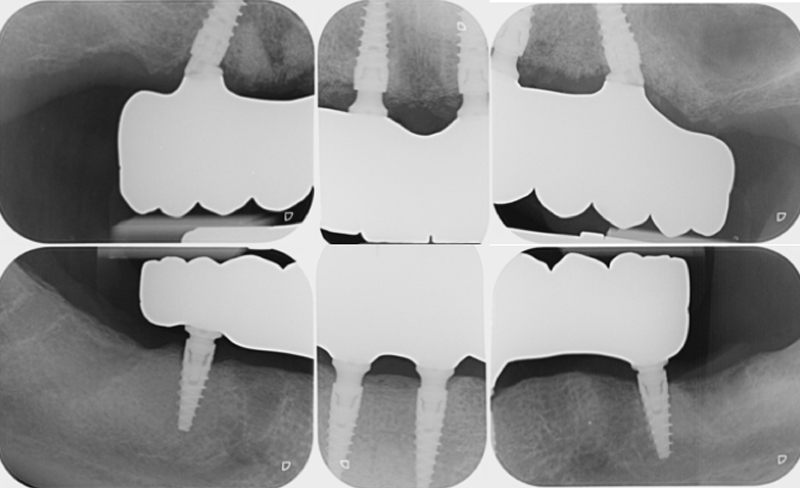

A circa tre mesi dal secondo intervento si procedeva alla realizzazione delle protesi definitive in zirconia integrale. Come già sottolineato, il work flow digitale per la realizzazione dei definitivi prevedeva una serie di tre appuntamenti. Durante il primo di questi venivano rilevate nuove foto extra-orali (Figure 5,6,7) e scansioni intraorali (TRIOS® 3, 3Shape) (Figure 8,9,10).

Le scansioni intraorali rilevate secondo la tecnica del flusso invertito erano:

• Arcata superiore con la protesi avvitata

• Arcata inferiore con la protesi avvitata

• Occlusione tra i provvisori

• Profilo gengivale dell’arcata superiore

• Profilo gengivale dell’arcata inferiore

• Arcata superiore con gli scanbody (IPD-AbutmentCompatibili) avvitati

• Arcata inferiore con gli scanbody (IPD-AbutmentCompatibili) avvitati.